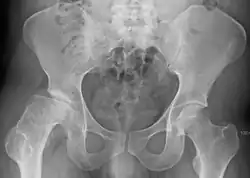

Radiograph of a person with Legg–Calvé–Perthes disease

X ray of deformity by Legg–Calvé–Perthes disease of the right hip (left side of X-ray)